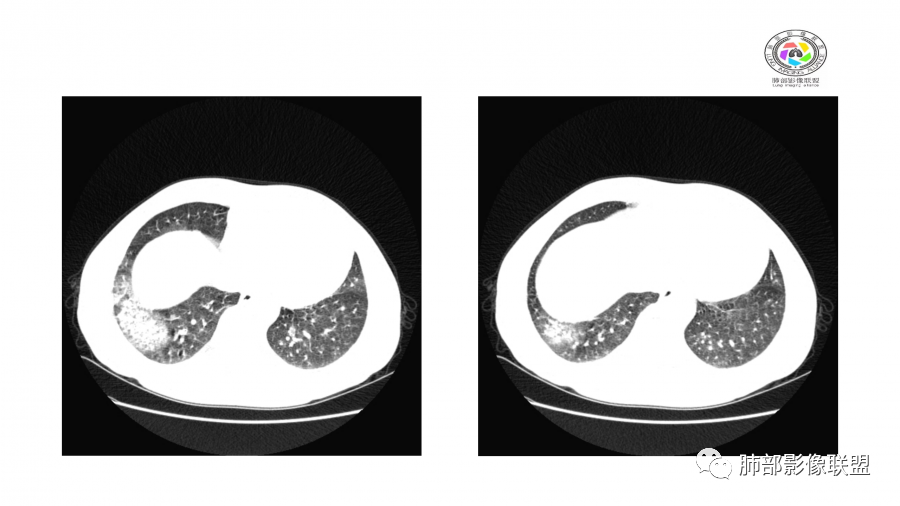

南边:

边界模糊,距离胸膜有间隙,内部支气管通畅

一月后:

病灶此起彼伏